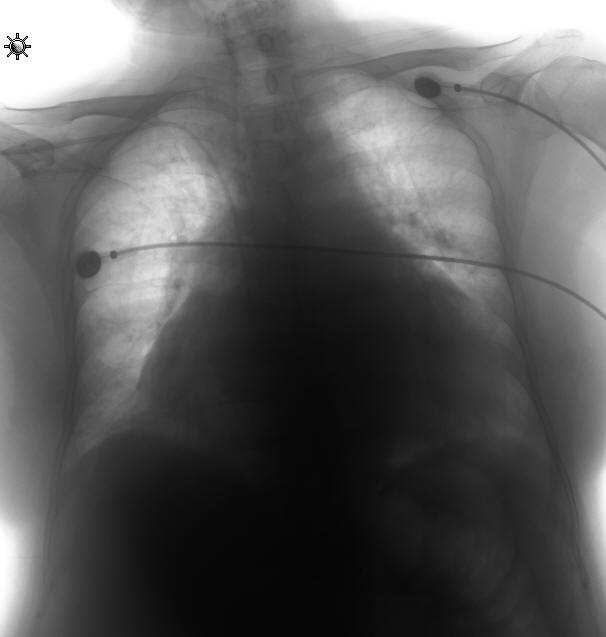

以下是引用前行在2008-4-27 19:28:00的发言:[br]慢性心功能不全

以下是引用dyqct在2008-4-27 19:22:00的发言:[br]心脏呈普大型,请结合临床听诊、心电图除外心衰。